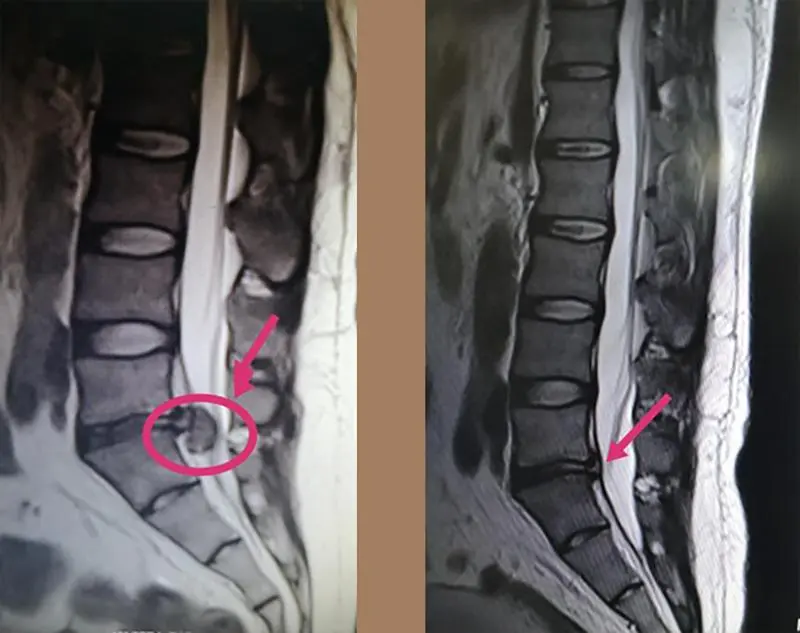

八、椎间盘突出胶原酶、臭氧、等离子靶点消融术

“靶点消融”,是指在影像设备(如DSA、CT)的精确引导下,将一根细针穿刺到突出的椎间盘或突出物内部/周围,注入特定物质,通过化学或物理反应,使突出的髓核组织缩小、溶解、萎缩或灭活,从而解除对神经根或脊髓的压迫,达到治疗目的。这三种技术均属于 “经皮穿刺微创介入治疗” ,用一根细针精准穿刺到病变椎间盘,通过 化学(胶原酶)、物理化学(臭氧)或物理(等离子) 的方式,使突出的髓核组织 体积减小、压力降低,从而解除对神经的压迫。

椎间盘突出胶原酶、臭氧、等离子靶点消融术的优点:

治疗前后影像对比图